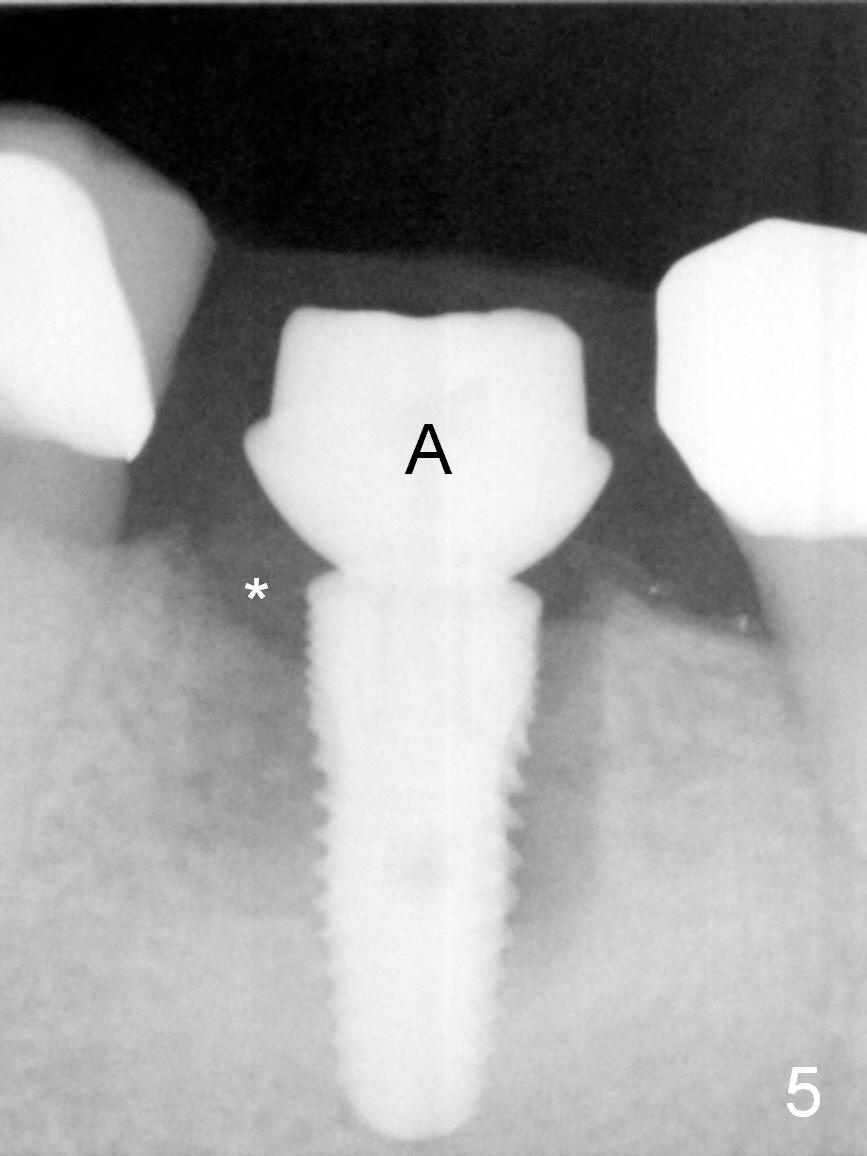

In fact, the buccal plate and the septum are defective. Osteotomy is initiated lingual to the center of the common sockets (Fig.1); depth is about 4 mm. When a 5x12 mm bone-level implant is placed (Fig.4), there is a gap mesiobuccally, which is later filled with bone graft (Fig.5 *). A large abutment (7.8x4(3) mm) is placed immediately (Fig.5 A) for an immediate provisional to close the sockets. The buccal abutment margin is ~ 1 mm subgingival, whereas the lingual ~2 mm supragingival. The abutment may need to be changed in the restorative phase (Fig.9,10).